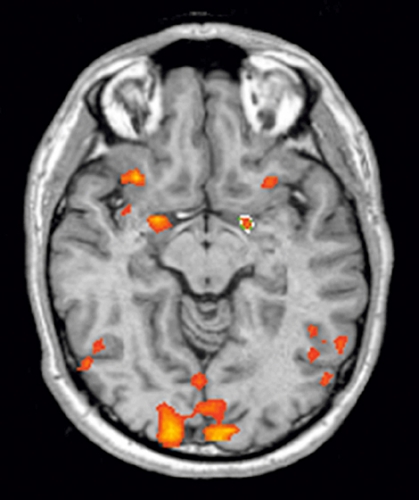

PET är en avbildningsteknik som bygger på emission av positronstrålar vid radioaktiva isotopers sönderfall. PET-teknik kan användas för att tex studera glukosmetabolismen i hjärnan. Resultaten från PET-studierna tyder på lägre glukosmetabolism i temporalloberna och frontalloberna, både i prefrontal- och i orbitofrontalkortex, hos våldsamma patienter [45, 46, 51].

Raine och medarbetare har publicerat flera resultat från en PET-studie av kriminalvårdsklienter dömda för mord i USA [47-50]. Dessa individer hade, enligt amerikansk lagstiftning, förklarats icke skyldiga till följd av psykisk sjukdom eller för sjuka för att delta i rättgång. De inkluderade fick genomgå ett uppmärksamhetstest som aktiverade frontalloberna samtidigt som deras hjärnaktivitet undersöktes med PET. Resultaten visade en signifikant lägre glukosmetabolism i mediala och laterala prefrontalkortex hos mördarna jämfört med en grupp friska kontroller [49, 50]. Då man i analysen kontrollerade för socioekonomiska faktorer under uppväxten visade det sig att endast de med en relativt stabil uppväxt uppvisade lägre glukosmetabolism prefrontalt jämfört med såväl den grupp som varit psykosocialt missgynnad under barndomen som en frisk kontrollgrupp [47].

I ytterligare analyser delades gruppen mördare upp med avseende på om de använt affektivt eller predatoriskt våld. Affektivt våld är reaktivt och impulsivt och följer som en direkt respons på stimuli. Fysiologiskt sett är det förenat med förhöjd autonom aktivitet [62]. Ett exempel på affektivt våld är en verbal konflikt som trappas upp till ett häftigt gräl och till slut övergår till slagsmål. Det predatoriska våldet däremot är mer instrumentellt, målinriktat och kontrollerat till sin natur och är inte förenat med ökat stresspåslag [62]. Exempel på predatoriskt våld kan vara en välplanerad hämndaktion som svar på en kränkning eller ett målinriktat våld, exempelvis i samband med ett bankrån.

Den grupp som använt affektivt våld uppvisade minskad glukosmetabolism prefrontalt men ökad högersidig metabolism subkortikalt, innefattande amygdala, hippocampus och talamus, jämfört med kontrollgruppen. Gruppen som använt predatoriskt våld uppvisade också ökad glukosmetabolism subkortikalt på höger sida men ett aktiveringsmönster mer likt kontrollgruppens i de prefrontala regionerna. Författarna tolkade detta som att ökad subkortikal aktivitet skulle vara förenad med aggressivt temperament och att det på så sätt hade funnits en bibehållen dämpande frontal aktivitet hos de individer som använt predatoriskt våld jämfört med dem som använt affektivt våld [48].